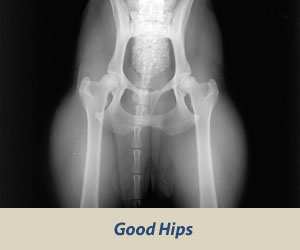

Výsledok (nález) sa označuje číslami 0-4 a písmenami A-E a je zaznamenaný pre každú končatinu zvlášť.

hips excellent hips good hips fair

A – negatívny stupeň

-anatomická pravidelnosť, žiadne príznaky dysplázie